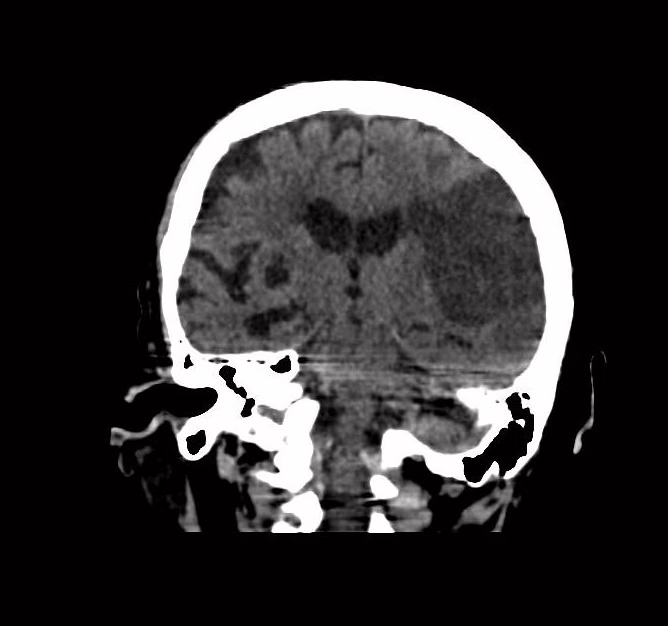

Sustancia gris y blanca, hacia lóbulo frontal, parietal y temporal izquierdos, con área hipodensa, irregular, bien definida, que mide 6.21 X9.27X 4.27 cm, en su eje longitudinal, anteroposterior y trasversal respectivamente, con leve efecto de masa hacia ventrículo lateral izquierdo. A nivel de lóbulo insular derecho, con pequeña área ovoidea, regular, bien definida, isodensa a líquido cefalorraquídeo, que mide 13.7 X 8.9 mm. Resto con adecuada diferenciación.

Surcos y cisuras, periférico área hipodensa de lóbulo frontal, parietal y temporal izquierdos con disminución de su amplitud y profundidad esto por edema citotóxicos. Resto con aumento de la amplitud y de profundidad.

Núcleos de la base, y núcleo caudado izquierdo, con área ovoidea, regular, bien definida, que mide 12.9 X 8.4 mm, con efecto de masa. Resto de morfología y densidad habitual, simétricos

EN EL PRESENTE ESTUDIO TOMOGRAFICO, EXISTEN EVENTO VASCULAR ISQUÉMICO AGUDO A NIVEL DE LÓBULO FRONTAL, PARIETAL Y TEMPORAL IZQUIERDO, ASÍ COMO TAMBIÉN EVENTO LACUNAR AGUDO A NIVEL DEL NÚCLEO CAUDADO IZQUIERDO, ESTOS CON EDEMA ASOCIADO.

EVENTO LACUNAR ISQUÉMICO CRÓNICO EN LÓBULO INSULAR DERECHO.

EVENTO VASCULAR ISQUÉMICO AGUDO A NIVEL DE LÓBULO FRONTAL, PARIETAL Y TEMPORAL IZQUIERDO